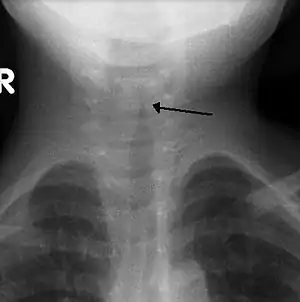

| The steeple sign as seen on an anteroposterior neck X-ray of a child with croup | |

In radiology, the steeple sign is a radiologic sign found on a frontal neck radiograph where subglottic tracheal narrowing produces the shape of a church steeple within the trachea itself.[1][2] The presence of the steeple sign supports a diagnosis of croup, usually caused by paramyxoviruses.[3] it can also be defined as the replacement of the usual squared-shoulder appearance of the subglottic area by cone-shaped narrowing just distal to the vocal cords. This is called the steeple or pencil-point sign.